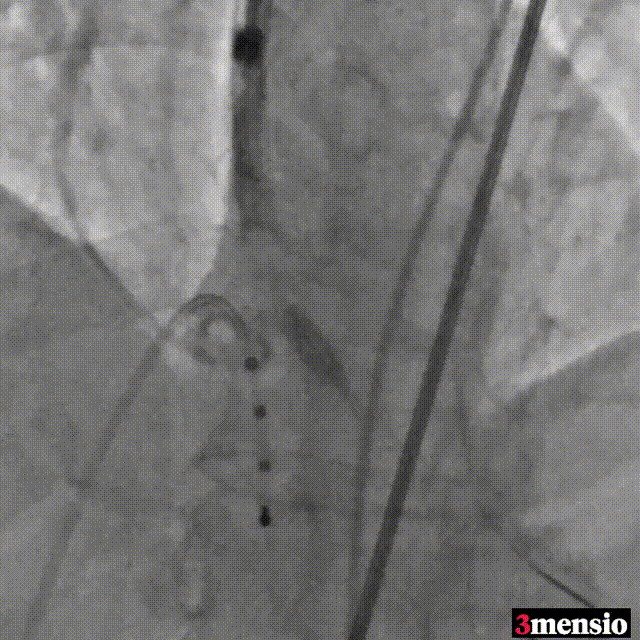

瓣膜稳定脱钩

瓣膜最终位置